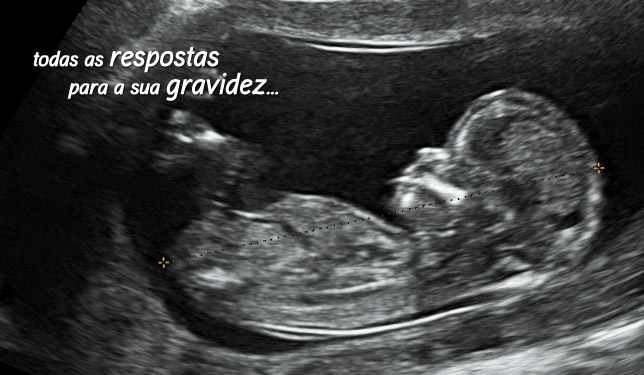

O Centro Ecográfico de Entrecampos (CEEC) tem vindo a desenvolver exames fundamentais no acompanhamento da gravidez, na avaliação ginecológica e no estudo da infertilidade.

Dedica-se principalmente à realização de ecografias, seguindo padrões de elevada qualidade, de forma a garantir a máxima fiabilidade diagnóstica.